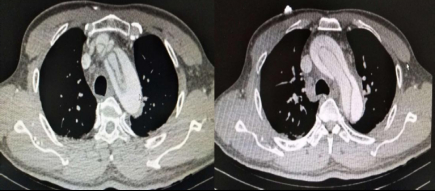

患者于当日23:50送达本院急诊抢救室。来院时神志不清,GCS评分7分,血压132/87 mmHg(1 mmHg=0.133 kPa),心率90次/min,呼吸22次/min,脉搏92次/min,血氧饱和度96%,血糖6.7 mmol/L。查体见面色红润,舌体咬破。两肺呼吸音清,未闻及干湿性啰音,心律齐,无明显病理性杂音,腹平软,压痛反跳痛难以配合,两侧病理征未引出。2019-01-02 23:58心电图示窦性心律,ST段改变(图 1A)。2 h后复查心电图示窦性心动过缓,ST-T改变,左室高电压、心电轴左偏,Ⅰ、Ⅴ5、Ⅴ6导联ST段呈水平型、下斜型压低,0.05~0.1 mV,Ⅴ1、Ⅴ2、AVR呈水平型抬高(图 1B)。(2019-01-03 00:15)床边检测cTnT 0.014 ng/mL,D-二聚体 > 10 000 ng/mL,NT-pro BNP 20 600 ng/L。2 h后复查cTnI 0.049 ng/mL。生化示肌酐284 μmol/L,其余指标未见明显异常。头颅CT示右侧颞枕叶条片灶,局部似与右侧脑室后角相连,脑裂畸形:合并灰质异位?软化灶合并脑穿通畸形?(图 2)。胸部CT示心脏增大、肺动脉高压,肺动脉主干增宽4.0 cm,心包前部少许积液。床边心超示:左室壁运动欠协调,室间隔运动稍减弱,主动脉瓣反流(轻度),EF为52%。患者入院后烦躁不安,先后予镇静、抗癫痫等治疗。因患者D-二聚体升高明显,胸部CT示肺动脉增宽明显、肺动脉高压,考虑存在肺栓塞可能; 另一方面,患者血压呈进行性上升,D-二聚体升高,CT示心包前部少许积液,故主动脉夹层亦不能除外,需行动脉造影明确,但因患者肌酐异常,存在慢性肾衰竭,行增强CT检查需注射造影剂,可能进一步加重肾损害,故家属拒绝。2019-01-03 07:00患者神志转清,诉有头晕,无胸痛,血压持续波动在200/100 mmHg左右,予镇静、降压效果均较差,病情反复告知家属,家属商议后最终同意行CTA检查。13:05行胸部增强+肺CTA示主动脉弓夹层(De Bakey I、Stanford A型),肺动脉高压(图 3)。最终患者诊断主动脉夹层(De Bakey I、Stanford A型)明确,因本院手术条件所限,当天即予转上一级医院手术治疗。

| 图 3 患者肺CTA示主动脉弓夹层(Stanford A型) |

本病例的诊断上存在干扰因素较多,容易有以下五个误区。误区一:易误诊为急性冠脉综合征。胸闷、心电图ST-T改变,加上高血压、糖尿病病史,接诊医生极易诊断为“急性冠脉综合征”,因基层医院条件所限无法完善心肌酶谱检查,更无法完成血管造影检查,所以导致了初步诊断的误诊。这也提示单凭主诉与心电图来诊断急性冠脉综合征是不严谨的。此外,心电图的缺血表现提示该患者冠脉可能有受累,但因患者未行PCI检查使得无法证实。误区二:易误诊为一般的癫痫或阿-斯综合征发作。患者癫痫样发作后来本院查头颅CT提示右侧颞枕叶存在条片状异常,且后来患者神志转清,故本院接诊医生考虑存在颞叶癫痫可能; 另一方面,予动态复查心电图、心肌酶谱存在异常,因此需与急性冠脉综合征所致阿-斯综合征发作相鉴别。有报道,部分病例中可将癫痫发作作为诊断脑梗死的首要依据[7]; 本病例考虑为夹层撕裂累及头臂干后致大脑循环低灌注,引起缺血性卒中,从而继发早发性癫痫。误区三:易误诊为肺栓塞。胸闷、D-二聚体升高明显、肺动脉明显增宽、肺动脉高压等特点,均提示存在肺栓塞可能,值班医生一度考虑急性肺栓塞并动员家属行肺动脉CTA检查。但患者血气未见低氧血症、心超未见右心增大、难以解释的癫痫样发作,诊断肺栓塞依据不充分,CTA检查可排除。提示对于存在肺动脉增宽伴肺动脉高压的患者,除考虑肺栓塞外,还要排除主动脉夹层。误区四:易受肌酐影响而放弃行CTA检查。该患者肌酐异常,存在慢性肾衰竭,行血管造影可能加重肾损伤,存在诱发造影剂肾病的风险[8]。若值班医生未多次劝说家属行CTA检查,该病例可能仍处在误诊之中,甚至在还未行CTA检查时患者就急性加重死亡,引起医疗纠纷。误区五:易漏诊主动脉夹层。该患者发病时无明显胸痛、背痛等典型的撕裂样疼痛,两侧桡动脉对称、心超未见假腔,极易漏诊,回顾病史,患者的血压持续处于高水平,结合D-二聚体及CT提示心包前部少许积液及肺动脉增宽,诊断主动脉夹层已有迹可循。这也说明床旁心脏超声在主动脉夹层诊断中的应用存在假阴性,临床医师在诊断此类疾病时需引起重视。